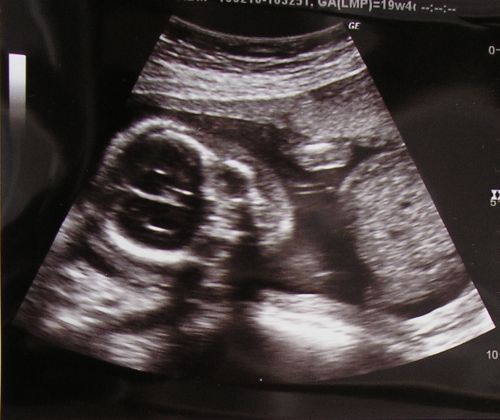

Barbuss: ha kész lesz majd tegyél fotót Emma új kuckójáról! Na meg hogy mi volt ma az UH-n